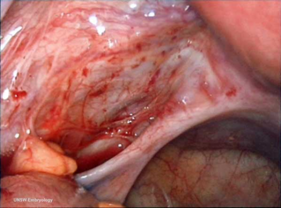

LNMTC phúc mạc mức độ tối thiểu (độ I) |

LNMTC phúc mạc mức độ nhẹ (độ II) |

LNMTC phúc mạc mức độ vừa (độ III) |

LNMTC phúc mạc mức độ nặng (độ IV) |